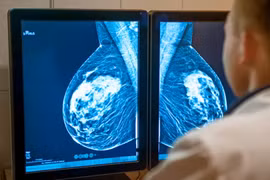

Ung thư vú là loại ung thư thường gặp gây tử vong nhiều nhất ở phụ nữ sau 35 tuổi. Phát hiện sớm ung thư vú rất quan trọng, giúp điều trị bệnh hiệu quả hơn.

Ung thư vú là nguyên nhân gây tử vong hàng đầu trong các loại ung thư ở phụ nữ trên thế giới. Tuy nhiên, có một số nhóm người có nguy cơ cao mắc ung thư vú.